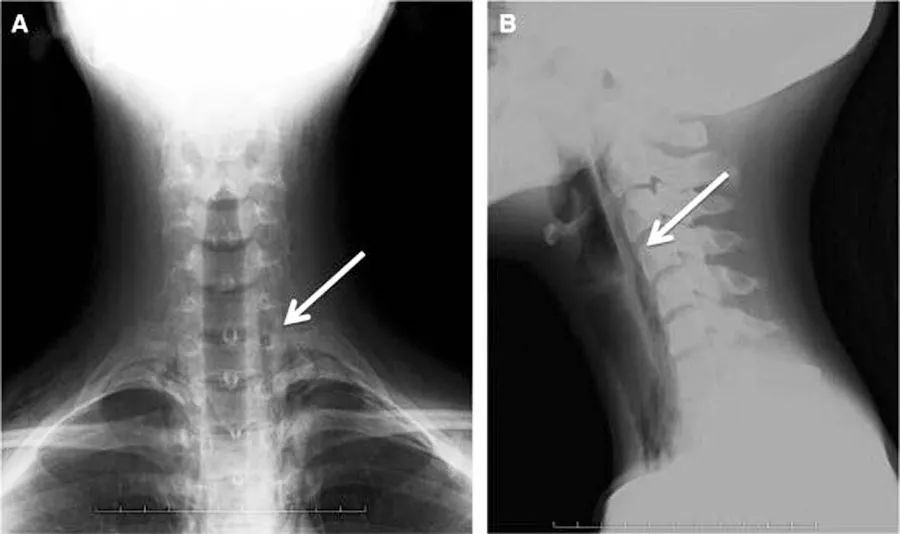

颈前和侧位X线片:气管旁和咽后间隙的漏气(图1,A和B)。